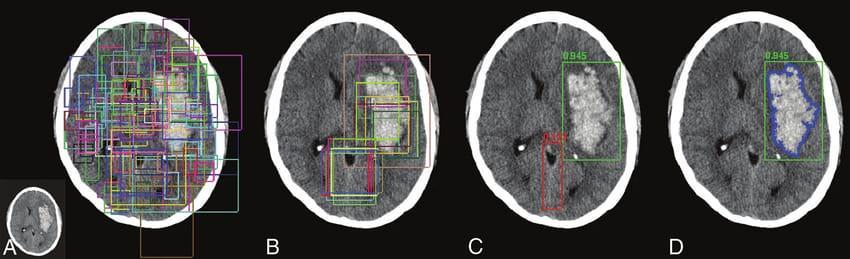

Region Proposal Network (RPN):

TheROI’scanbegeneratedbyfeedingthefeaturestoRPN.To representaboundingboxofvarioussizesthatisdistributed all over the images can be obtained by a 3*3 Convolution layer which scans the images using sliding window. To identify the anchor contains back ground or object binary classification of the image takes place. For setting IOU (Intersection Over Union) values the bounding box regressiongivesboundingboxes.IOUvaluegreaterthan0.7 canbeidentifiedaspositiveorelsenegative.

Bounding Box Regression and ROI Classification:

This stage takes the input from the ROI proposal and classifies the images deeper into tumour or non tumour. Later enhances the size of bounding box. To specifically identifythetumourregionbasedonlocationandsizecanbe donebyBBR.Toobtainthecorrectlengthvectorsoffeature fortheregionsofarbitrary sizeROIAlignlayerisused.

Segmentation Mask:

ThesegmentationmaskobtainstheinputfromtheROIAlign thatisofthetypeofpositive.Itidentifiesthemaskfromthe positiveimageduringthetrainingstage.Thepositiveinput obtained from the ROI Align is fed to the Fully Connected Network(FCN)andthenthemaskisidentified.Finally,the outputmaskisobtainedfromthebrainimage.

MaskRCNNProcessthebrainMRIimagesin4Steps. MRIimagesareprovidedasInputtothealgorithm

STEP A:InthisstepSemanticSegmentationofthepixelsin thebrainMRIimagestakesplace.

STEPB: In this step Classification and localization of the PreferredlocationoftheMRIpixelimagesoccurs.

STEP C:Inthisstepmoreaccuratepreferreddetectionofthe specifiedlocationtakesplace.

STEP D: In this step the specific location of the tumor is obtainedasresult.